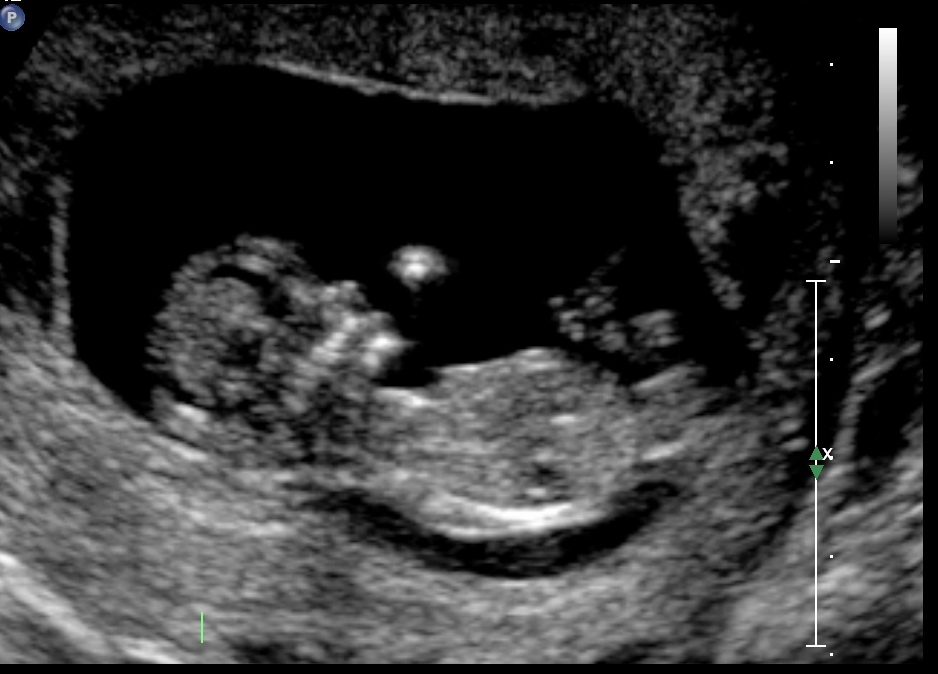

After 6 boys we are really hoping for a girl. Can any one please take a guess. :-)

Attachment 21858

I'm new at this but in 3rd pic it looks like a girl to me. Congrats on your baby xxxxxx

Last pic looks girly, congrats!

I'm wondering if the 3rd pic is showing an angled boy nub ontop of the main white line?? I may lean boy on this one but hope its your girl for you!!!